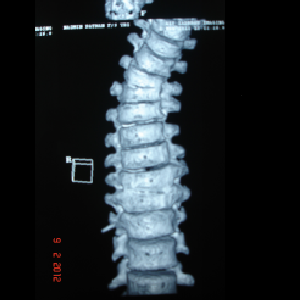

Double cord syndrome – DIASTOMATOMYELIA – is a very rare entity, wherein patient

is having congenital deformity of spine with separation of the spinal cord into

two halves by a bony or fibrous septum It is a great challenge to operate these

pts as , if something goes wrong, pt would become paraplegic for her life time.

Perticularly, in this case, as pt was only 9 years old and having congenital deformity

of the vertebrae, it was corrected simultaneously at Sola civil hospital - ahmedabad.

Hemivertebra Resection